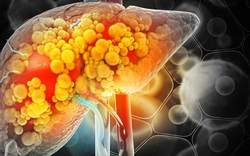

• Gan thận

• Ngày càng nhiều người còn trẻ đã khổ sở vì bệnh gan, bác sĩ nói thẳng: 4 loại hạt này ăn nhiều "phá gan" hơn bia rượu

Ngày càng nhiều người còn trẻ đã khổ sở vì bệnh gan, bác sĩ nói thẳng: 4 loại hạt này ăn nhiều "phá gan" hơn bia rượu